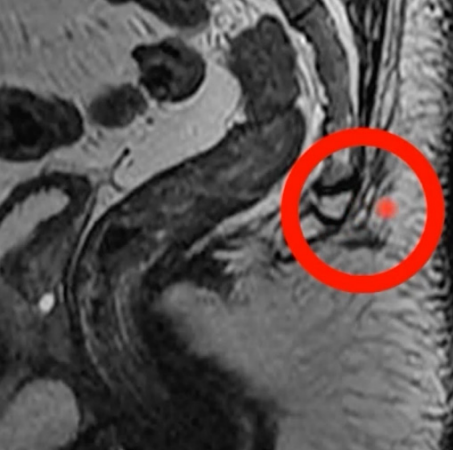

• Ressonância Magnética (RM): Considerada o padrão-ouro para avaliação de trajetos fistulosos complexos. É particularmente útil por fornecer uma visualização mais adequada dos reparos anatômicos da região.

Case courtesy of Varun Babu, Radiopaedia.org, rID: 57299 Visualização de pequena coleçåo pré-sacral em íntimo contato com subcutâneo região interglútea